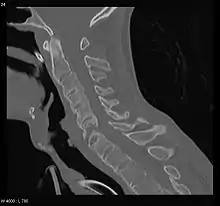

- (X-ray) للعمود الفقريّ قد يُظهر تسوية للفقرات مع تصلُّب في العمود الفقريّ وتكوُّن ناتئٌ عظميٌّ رباطيّ مما يؤدي إلى ما يعرف بالسيساء الخيزارانيّة(bamboo spine).

- من سيئات استخدام صور الأشعة السينية(X-ray) في التشخيص هو أن التغيرات تبدأ بالظهور على الصورة بعد.

فترة متأخرة من بداية المرض الفعليّ عند المريض قد تصل من 8-10 سنوات حيث يتأخر بها التشخيص وتتأخر عملية المعالجة بالأدوية لذلك، يستخدم التصوير المقطعيّ المحوريّ المحوسب(tomography)، والتصوير بالرنين المغناطيسي (MRI) للمفاصل العجزيّة الحرقفيّة للتشخيص المبكر ولكن، مدى دقة هذه الأدوات ما زالت غير واضحة تماماً.

قد تكون الجراحة من الخيارات للعلاج في الحالات الشديدة من المرض حيث يتم استبدال المفصل المصاب، بالتحديد في مفصل الركبة والكتف. التصحيح بالجراحة قد يساعد في حالات وجود تشوه في ثني العمود الفقري بالتحديد في منطقة الرقبة (حيث يكون هنالك انحناء شديد للأسفل)، مع العلم أن هذه العملية تعتبر من العمليات الخطيرة.

بالإضافة إلى ذلك، قد يؤدي إلتهاب الفقار المقسط إال بعض الأعراض التي تجعل عملية التخدير أكثر صعوبة. تغيرات في المجرى التنفسي العلوي قد يؤدي إلى خلق صعوبات في عملية إدخال أنبوب في المجرى التنفسي، التخدير في العمود الفقري أو فوق الجافية قد يكون أمراً صعبا بسبب تكلّس الأربطة، وعدد قليل من الناس المصابين بالمرض يعانون من قصور في الشريان الأبهري. قد يؤدي التصلب في اضلع الصدر إلى الاعتماد على عضلة الحجاب الحاجز بشكل رئيسي في التنفّس، لذلك قد يحدث قصور في وظيفة الرئة.